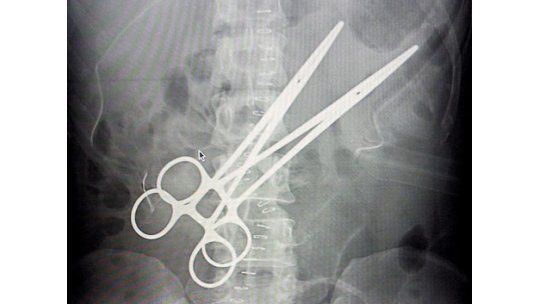

Dos médicos retiraron a una mujer boliviana unas pinzas de 16 centímetros que estuvieron en su abdomen durante 16 años, desde que fue sometida a una cirugía de vesícula en la ciudad central de Cochabamba.

Las pinzas quirúrgicas, que en las ecografías parecen tijeras, estuvieron "encapsuladas" durante todo el tiempo por una carnosidad que protegió la vida de la paciente, lo cual mostró a los médicos "lo maravilloso del cuerpo humano", dijo la abogada.